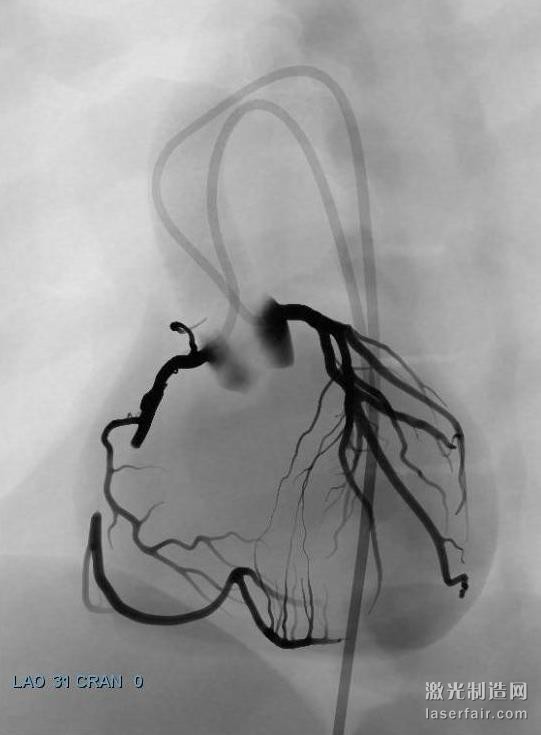

據(jù)了解,當(dāng)前在介入心臟病學(xué)領(lǐng)域出現(xiàn)了重要的新進(jìn)展,意味著更多的患者可以通過經(jīng)皮冠狀動(dòng)脈介入(PCI)技術(shù)來治療,該技術(shù)比其它心臟手術(shù)的侵略性更小。然而,每一個(gè)重要的技術(shù)發(fā)展,都意味著心臟病專家需要學(xué)習(xí)新的技術(shù),顯然光看說明書是不夠的。為了向有經(jīng)驗(yàn)的心臟病專家提供關(guān)于這些新技術(shù)的培訓(xùn),3DS開發(fā)的虛擬現(xiàn)實(shí)訓(xùn)練場景可以在其 ANGIO Mentor血管腔內(nèi)模擬器上使用。這些特定的場景包括冠狀動(dòng)脈CTO(慢性完全閉塞)治療和冠狀動(dòng)脈分叉例等。

關(guān)于慢性完全閉塞(CTO)病變的先進(jìn)的冠狀動(dòng)脈介入治療場景(使用ANGIO Mentor模擬器)